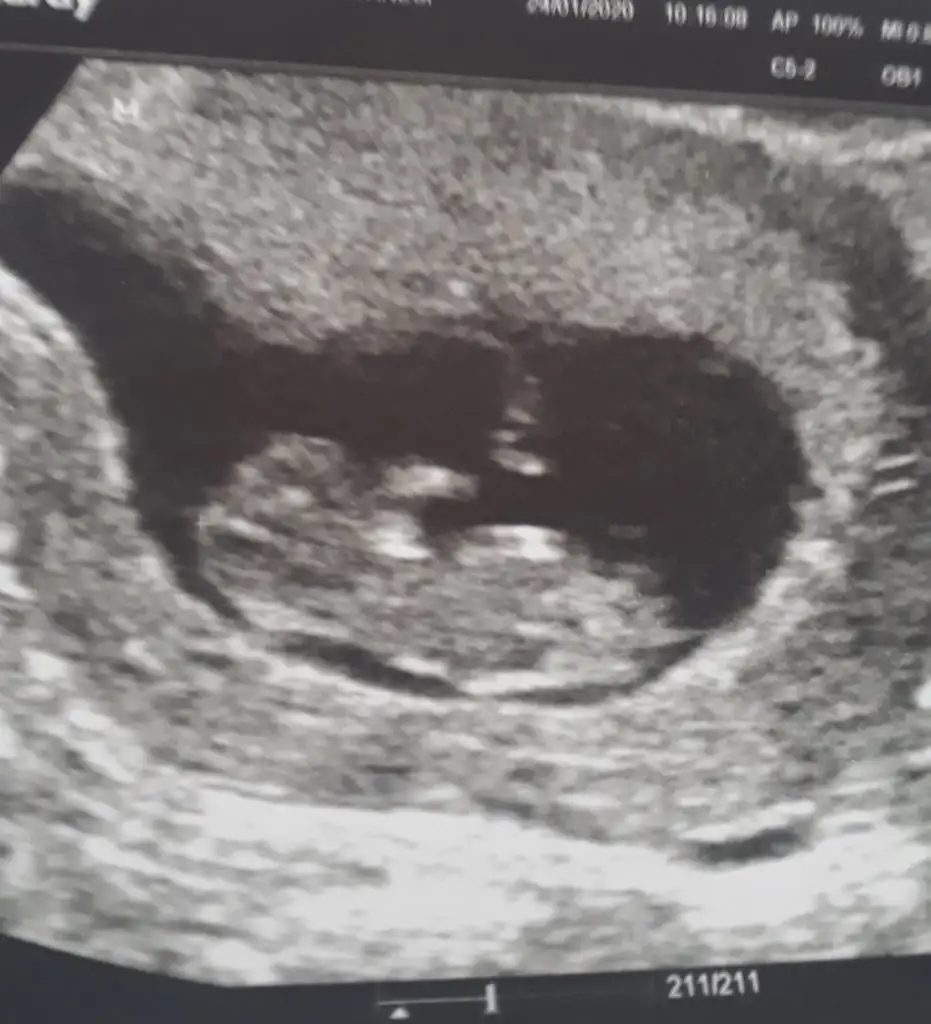

Erkekmı bebegınızBenim ne sizce :)

Kaç haftalık kız sanki ama kafa yapısı erkek nub kızEki Görüntüle 2580588 ikracım buda arkadaşın bakabilirmisin

Doktor da kız gibi demiş canım 14 haftalık burda. Benimkinin kafası kime benziyordu kafası ile ilgili yprum yapmadınKaç haftalık kız sanki ama kafa yapısı erkek nub kız![]()

Kız cnmDoktor da kız gibi demiş canım 14 haftalık burda. Benimkinin kafası kime benziyordu kafası ile ilgili yprum yapmadınEki Görüntüle 2580693 Eki Görüntüle 2580704